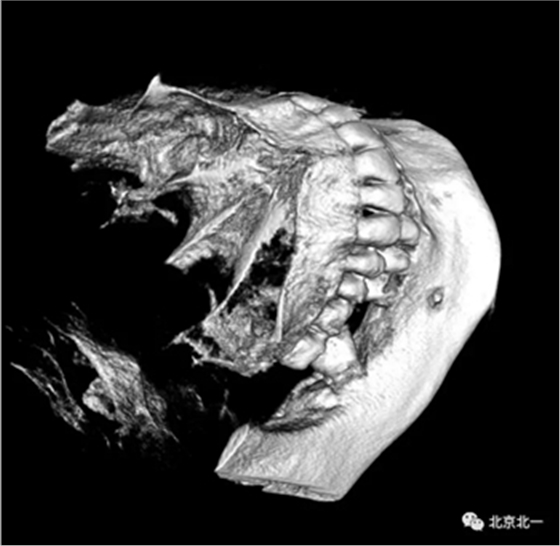

CBCT:骨量高度及宽度可, 48埋伏,低位阻生.37近中骨吸收

治疗计划:46种植, 同期拔除48 正畸扶正47.